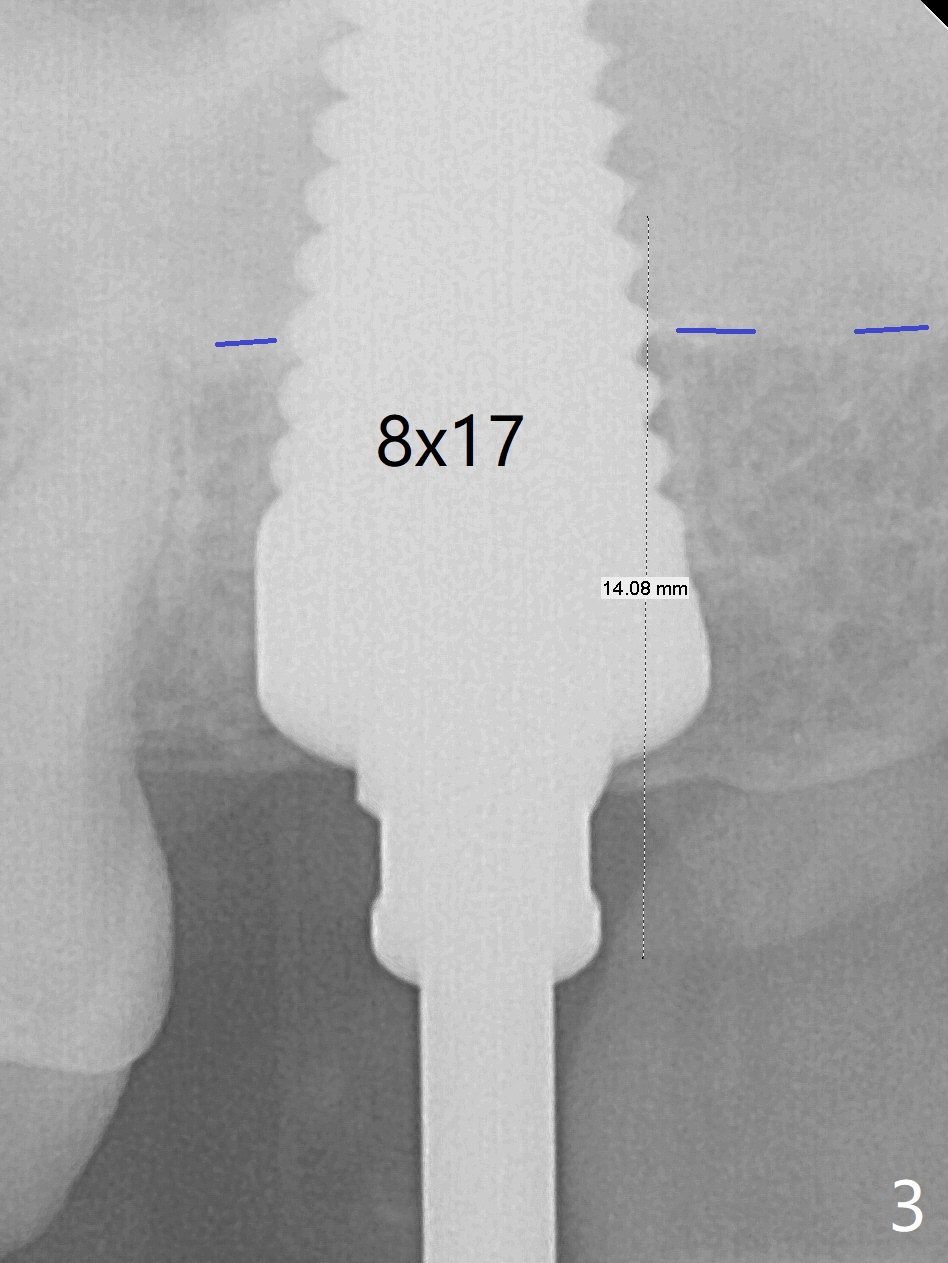

Initially the patient is reluctant to have the crack tooth extracted (Fig.1). Blood drawing for PRF fails. After extraction, the septum is confirmed to be short and thin. The bone density is moderate. When a 3.5 mm drill is being used, the osteotomy perforates into the mesiobuccal socket. A 5x10 mm IS implant achieves minimal stability. As 5.5, 6.0 and 7.0 mm cortical taps are inserted, primary stability is not obtained, as more bone is being removed at the level of the septum. When a 7x17 mm Tatum tapered tap is placed, it looks too small for the socket, as confirmed by measurement of a preop PA (Fig.2). Chronic infection associated with crack syndrome for 2 years may cause bone loss of the socket walls. Since the primary stability of a 8x17 mm tapered tap is not high (Fig.3), a 8x14 mm cylindrical implant is placed (after try in of its dummy one) with > 50 Ncm (Fig.4). The implant engages into the mesial and distal socket walls for stability. A 6x3 mm abutment is placed for an immediate provisional. In spite of difficult manipulation, the sinus membrane remains intact. Vanilla graft is placed for sinus lift and buccal and palatal gaps. Since IS implants are more or less cylindrical and if a 5 mm one does not achieve primary stability, a larger Tatum tapered tap should be tried immediately without using IS cylindrical taps. The patient returns 3 months postop, requesting early restoration before a trip to home country. The provisional has occlusal perforation. Final restoration is cemented nearly 4 months postop (Fig.5,6). The large implant makes the early restoration possible. However there is bleeding on probing palatal 1.5 years post cementation (Fig.7), suggesting palatal thread exposure. Return to Upper Molar Immediate Implant, Prevent Molar Periimplantitis (Protocols, Table), Armaments 6 Xin Wei, DDS, PhD, MS 1st edition 05/07/2018, last revision 05/08/2021